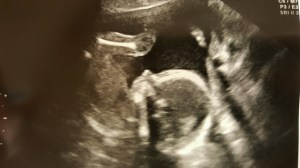

Today marks Day 8 since the retrieval and Day 3 since the transfer. Both went great… a complete rundown – we had 10 eggs retrieved, 7 eggs fertilized, 2 embryos frozen and one embryo transferred.

I did not produce as many follicles as I would’ve hoped, probably because of my low AMH levels. Generally, the retrieval is canceled if the patient doesn’t produce at least 5-15 follicles and the doctor was only counting 5-6 follicles for me on the ultrasounds, which is why our retrieval was about three days past our initial plan.. to give me more time to grow the existing follicles. Apparently God and the doctor know what they’re doing because we were very pleased to have retrieved 10 eggs! Most, well, maybe not most, but it’s not uncommon for women to have 20-30+ eggs retrieved.

So, by the Day 5 transfer, we could make a more educated “guess” as to which embryos are the strongest, healthiest options for us to transfer since the embryos had gone through the blastocyst stage. Another benefit of the Day 5 Blast is a lower risk of multiple pregnancies. If we had thrown in (sorry, I get casual with my vocabulary when discussing this sometimes) transferred two embryos on Day 3 and happened to have chosen the perfect two, we would have a higher chance of being blessed with twins. However, with the Day 5 transfer, we knew we had one embryo that was strong and powerful and perfect, so we only transferred that one, which significantly decreases the chances of twins since this would require the embryo to split, instead of just implanting two. Am I doing a terrible job of explaining this because I feel like my words are jello and lack substance here? Plus, I’d used to explaining this in person and for some reason, I feel like people understand it (or are better fakers in person) when I use my hands and arms to explain…